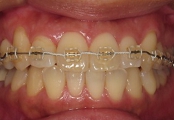

当院での咬合治療は,状態や原因に応じて様々なシステムを組み合わせて行っています.このケースでは,前方型のスプリントにて下顎位の精査と誘導を行った後に,固定式の矯正装置(拡大装置とマルチワイヤー装置)で,対応させていただきました.

←拡大矯正治療中.

歯列幅を,治療シュミレーションから設定した数値まで,効果的で迅速な矯正装置(緩徐拡大or急速拡大)を選択して左右的に拡大しながら,前歯の状態を整えています.

←ワイヤー矯正中

治療前と比較すると下顎は,強制的に後方に押し込まれた位置から開放されたらしく,自然に前方位を表してきました.

さらに,この下顎位にて上顎の後方歯および下顎にもワイヤー矯正を施しバランス矯正治療は終了となりました(非抜歯矯正)↓.